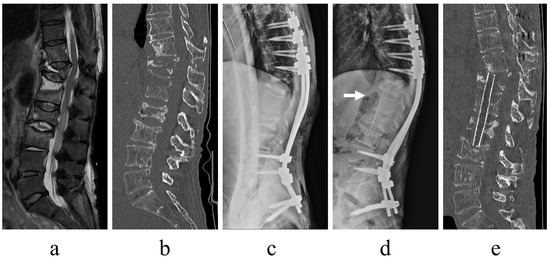

- Infection control. With minimally invasive posterior fixation and sensitive antibiotics, the inflammatory response normalized at an average of 42.8 days postoperatively. Previous reports stated that the period of normalization of the C-reactive protein concentration ranged from <1 month to 3 months; however, it was 42.8 days in this series [5,16]. In numerous patients, infection control was achieved without requiring additional surgery, thus implying that this technique is useful for infection control.

- Alignment maintenance. Local kyphosis, which is exacerbated by the destruction of the disk or vertebral body due to infection, is a measure of alignment maintenance. Minimally invasive posterior fixation improved local kyphosis by 6.6 degrees, with a postoperative correction loss of 3.6 degrees, which is comparable with results reported in previous studies (range: 3.4–6.8 degrees) [11,15,16]. These findings suggest that the range of fixation and fixation strength in this series were sufficient to maintain local alignment.